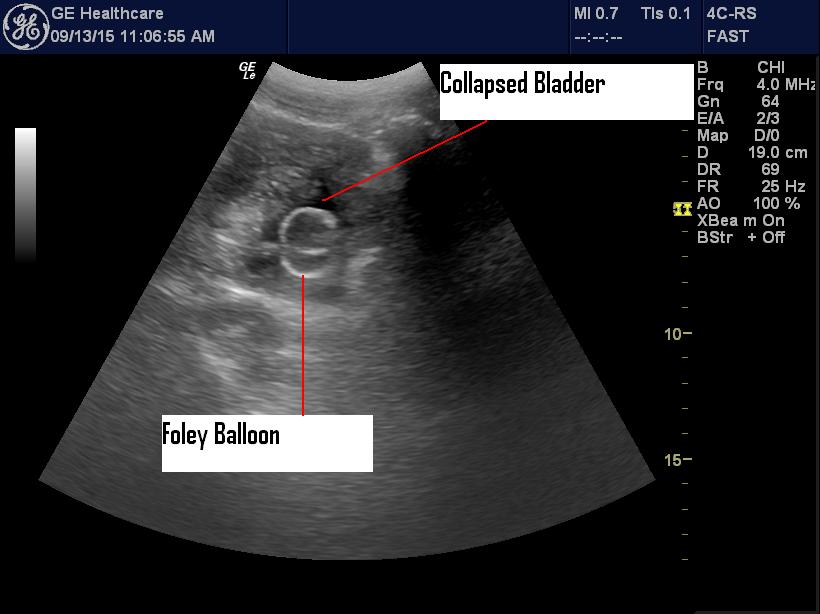

It still wouldn’t inflate, so I pushed it a touch further and sure

enough the balloon inflated and the patient was able to go home (after

disimpaction, rehydration, etc.)

Yup, agree. There are a lot of prostates and other tissues that have been shredded over the years by balloon inflation when the Foley hasn’t been advanced far enough or has created a false passage. Routine POCUS prior to balloon would drastically reduce these misadventures. This is not something that the “Bladder Scanner” device can do. This case illustrates that even when urine returns, the tip of the tube may not be in the bladder. There have been 3 EDE RN Courses so far. Lots of work still to do!